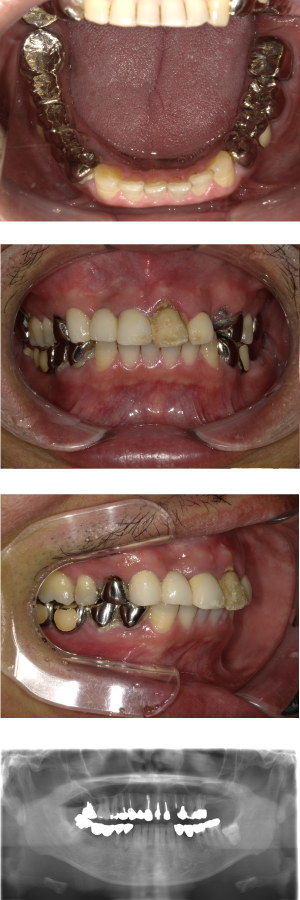

50代 インプラント治療(右上3左上3のみGBR)

| 年代・性別 | 50代・男性 |

|---|---|

| 主訴 | 入れ歯が合わず毎日ヨーグルトしか食べることができないので、しっかり咬めるインプラントにしたい。 |

| 部位 | 右下⑦⑥5④ 上顎③2①①2③ 左下67 |

| 治療期間 | 約9ヶ月 |

| 費用 | ¥4,273,500(税込) |

| 副作用・リスク |

|